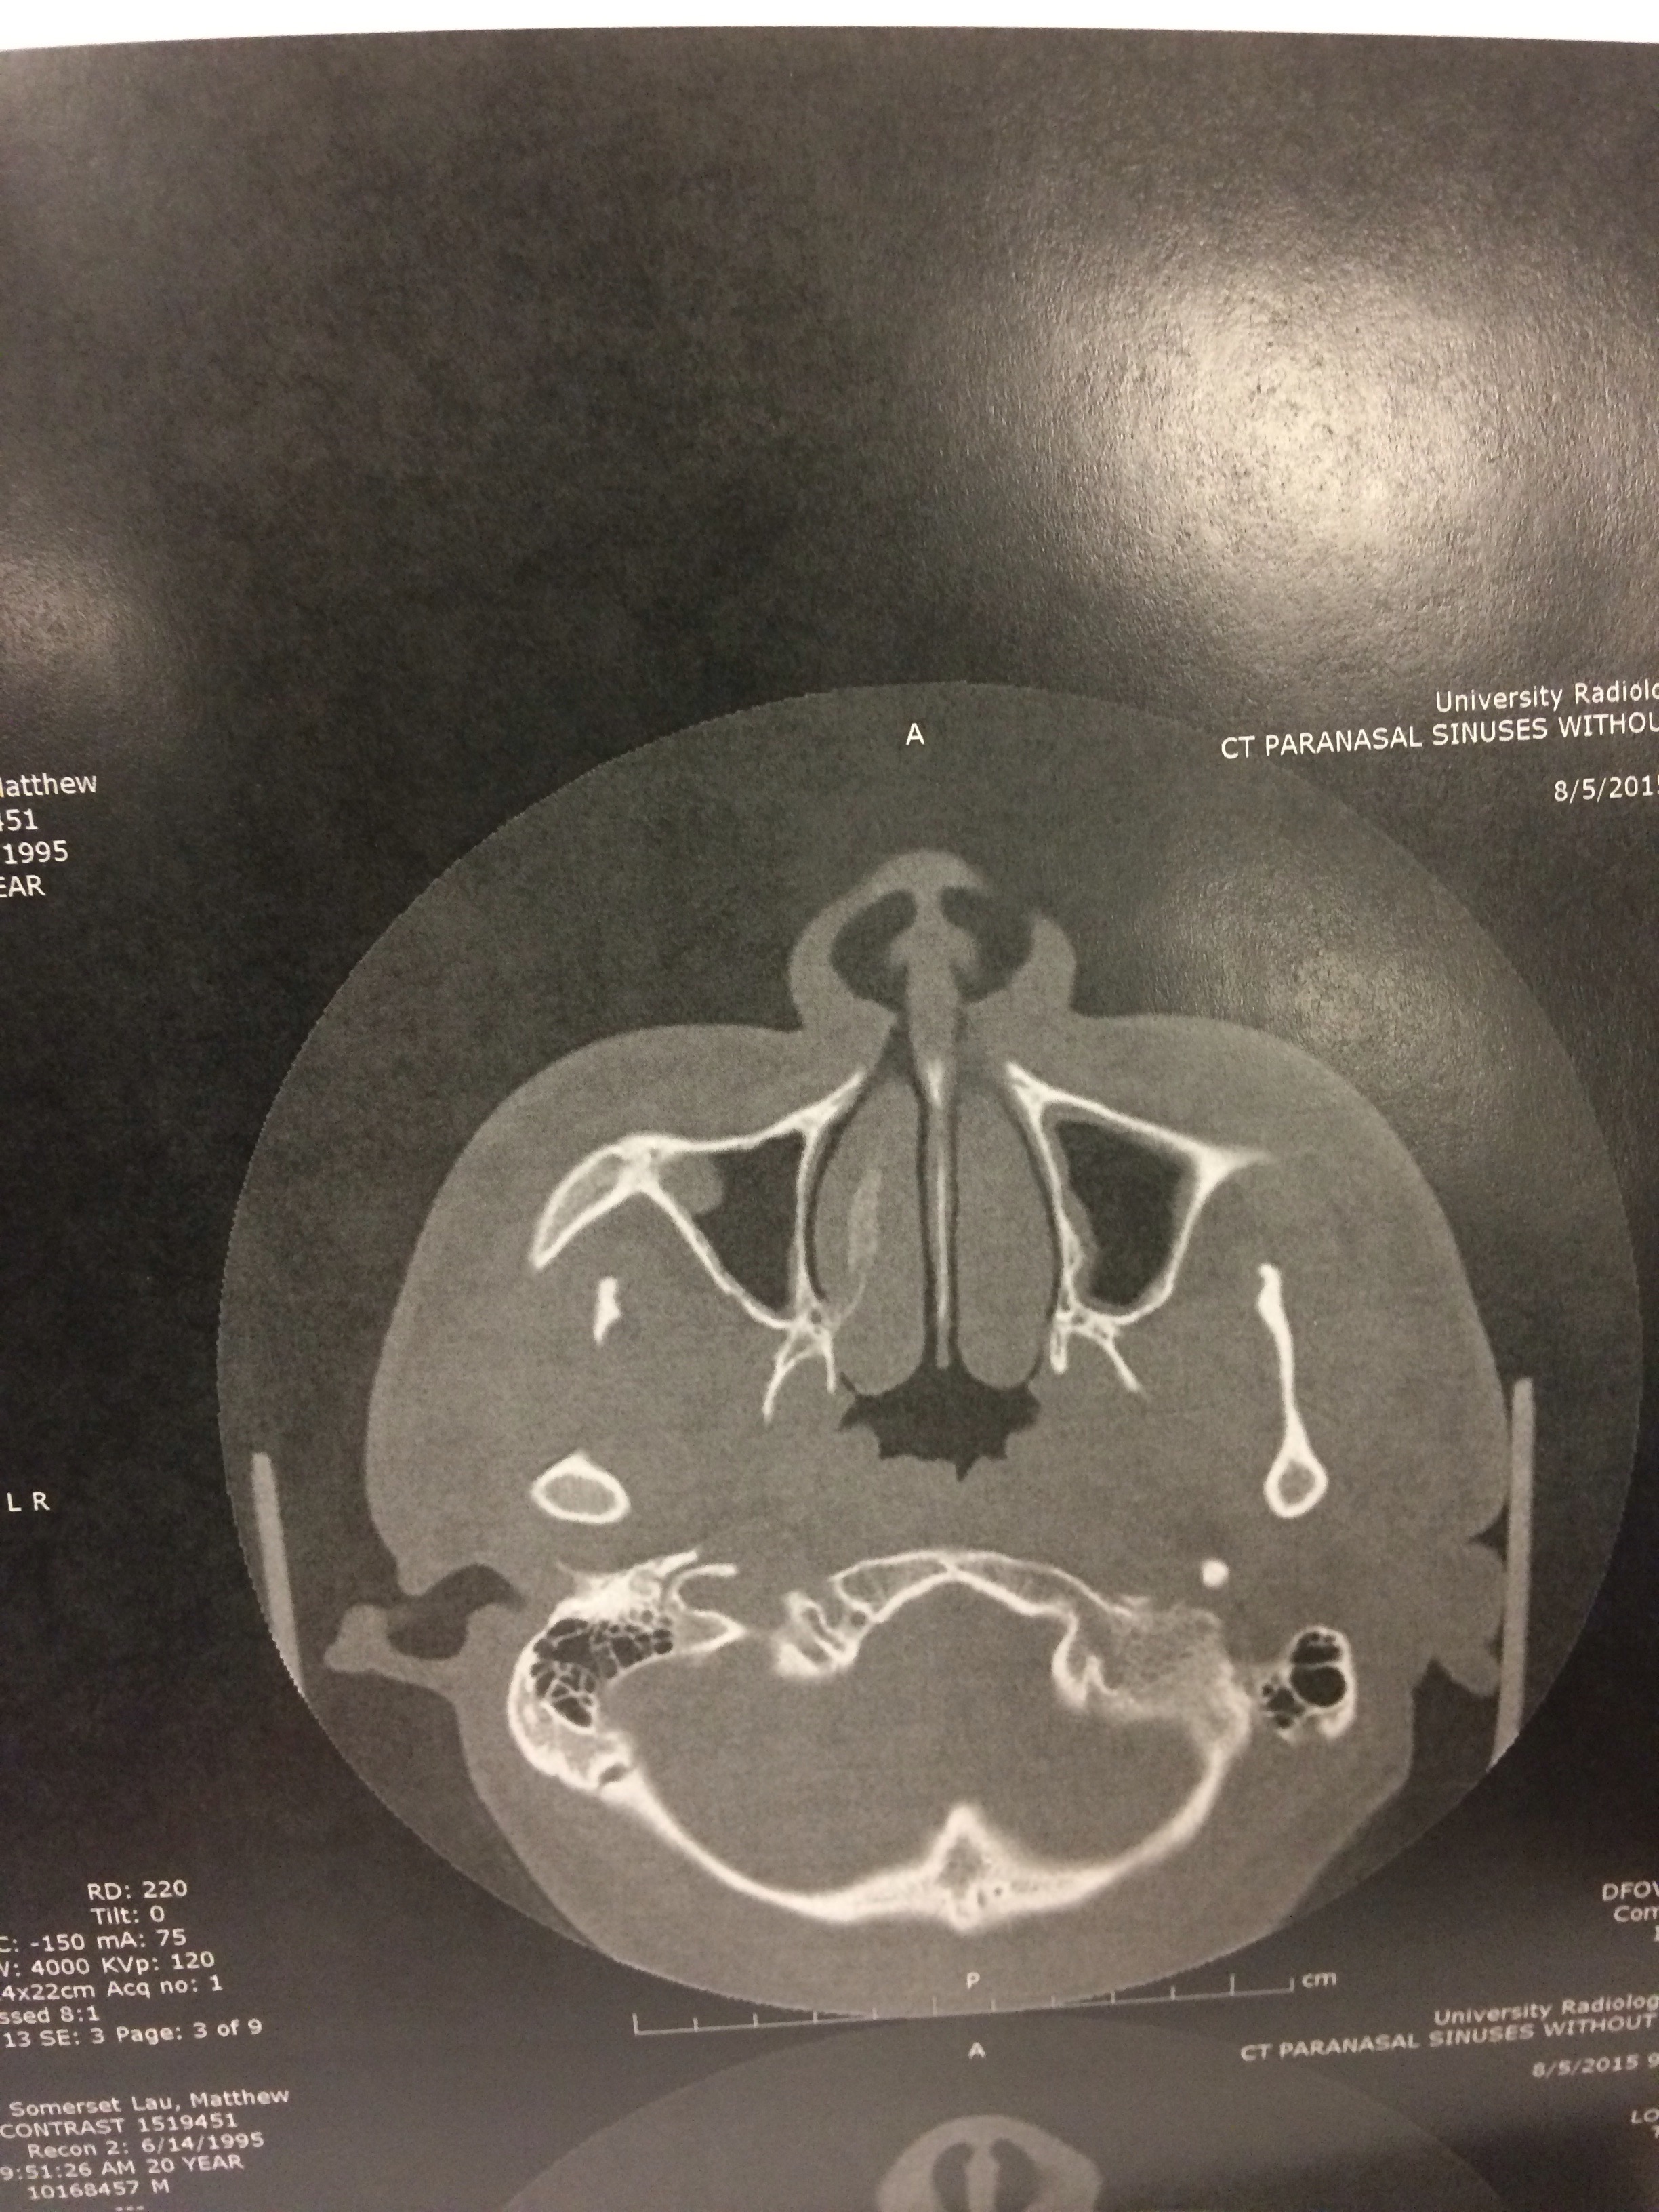

This is a surgery to fix my deviated septum. I like to think a “deviated septum” as a doctor’s nice way of a describing a crooked nose. The septum is the structure the two nostrils, and mine is deviated so much that it affects my breathing very negatively, and also makes it very easy to have a sinus infection with all the congestion. This is also causing a sort of sleep apnea at night because of the hindered breathing, not allowing enough oxygen into my body when I sleep at night.

Here’s one of the many cat scans of my head, haha.